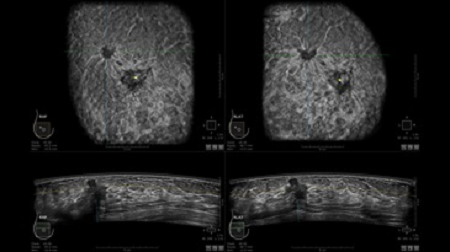

GE INVENIA ABUS – это современный УЗИ аппарат, который создан для точной и эффективной диагностики сканирования с высокой плотностью молочных желез. Выявляемость патологий раковых и предраковых стадий заболевания составляет 55%, что в конечном счете позволяет ставить врачу точные и своевременные диагнозы. Традиционные методы использования маммографии не показывают такой выявляемости, ограничиваясь лишь 3-38%.

УЗИ-аппарат GE INVENIA ABUS позволяет проводить максимально операторонезависимые процедуры, что значительно снижает риск неправильной постановки диагноза и сопутствующие издержки на обработку информации. Система готовит отчет в течение 3-х минут после сканирования, это безусловное преимущество по сравнению с обычным УЗИ сканером.

• Получение объемных 3D изображений с возможностью покадрового просмотра

• Получение изображений в поперечной плоскости (в реальном времени) и в коронарной плоскости (статическая, для указания нахождения соска)

• Отображение объемных 3D ультразвуковых изображений, которые состоят из традиционных поперечных и воссозданных коронарных и сагиттальных проекций

• Стандартизованная ориентация изображения: «толстый срез» в коронарной плоскости; поперечная; сагиттальная плоскость; радиальный и антирадиальный поворот изображения; просмотр исключительно области интереса